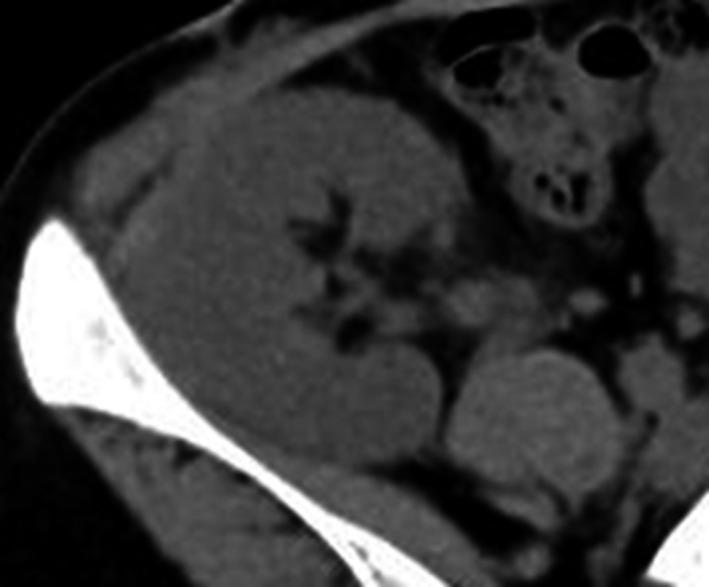

This case pertains to a 26-year-old woman who was diagnosed with congenital hypoparathyroidism 1 month after birth, following which vitamin D supplementation was initiated. In 20XX, she developed nephrocalcinosis and was confirmed to have a mutation; hence, she was diagnosed with hypoparathyroidism, sensorineural deafness, and renal dysplasia syndrome. In 20XX + 7, ABO-incompatible living-donor kidney transplantation was performed. Her renal function improved, and graft calcification was not observed.

Over intake of vitamin D caused nephrocalcinosis. The renal function was improved after living-donor kidney transplantation and the patient's serum calcium levels normalized without vitamin D supplementation. Therefore, kidney transplantation should be considered a treatment option for patients with hypoparathyroidism, sensorineural deafness, and renal dysplasia syndrome.